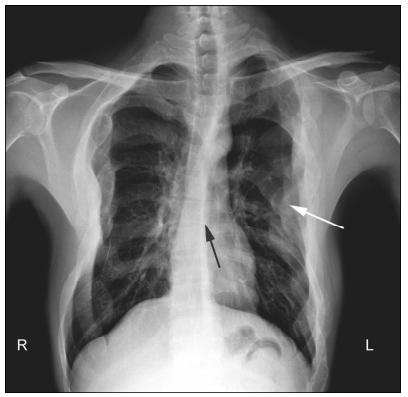

Preoperative routine X-ray chest analysis demon-strated evident scoliosis and multiple local enlarge-ments of the ribs (Figure 2). Because of a lack of any symptoms of the limbs and cavitas pelvis, X-ray analysis of these regions was not performed. No café-au-lait cutaneous spots were found on the patient. The patient did not have any symptoms related to endocrine abnormalities. Levels of related serum hormones were not tested. Without café-au-lait cuta-neous spots and endocrine abnormalities, polyostotic FD was diagnosed instead of MAS.

| Figure 2 X-ray chest analysis demonstrating scoliosis (black arrow) and multiple local enlargements of the ribs (white arrow). |